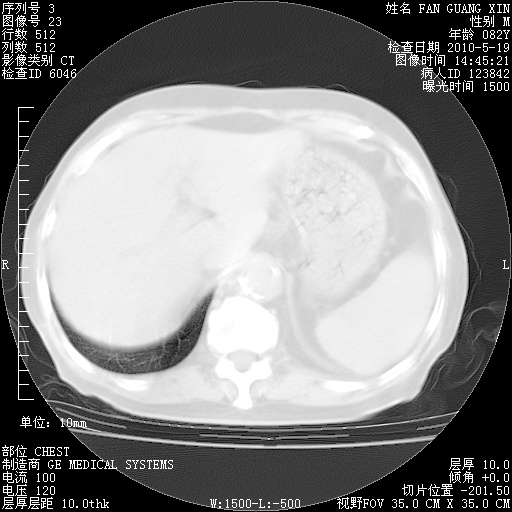

可改为口服强的松40-50mg/d治疗,若病情仍稳定,胸部阴影不再吸收可逐渐减量